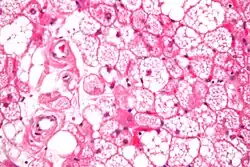

Micrograph of a hibernoma. H&E stain.

The tumors histologically resemble brown fat. There are four histologic types recognized, but one is the most frequently seen (typical). There is a background of rich vascularity.

1. Lobular type: Variable degrees of differentiation of uniform, round to oval cells with granular eosinophilic cells with prominent borders, alternating with coarsely multivacuolated fat cells (pale cells). There are usually small centrally placed nuclei without pleomorphism. The cells have large cytoplasmic lipid droplets interspersed throughout.[4][5]